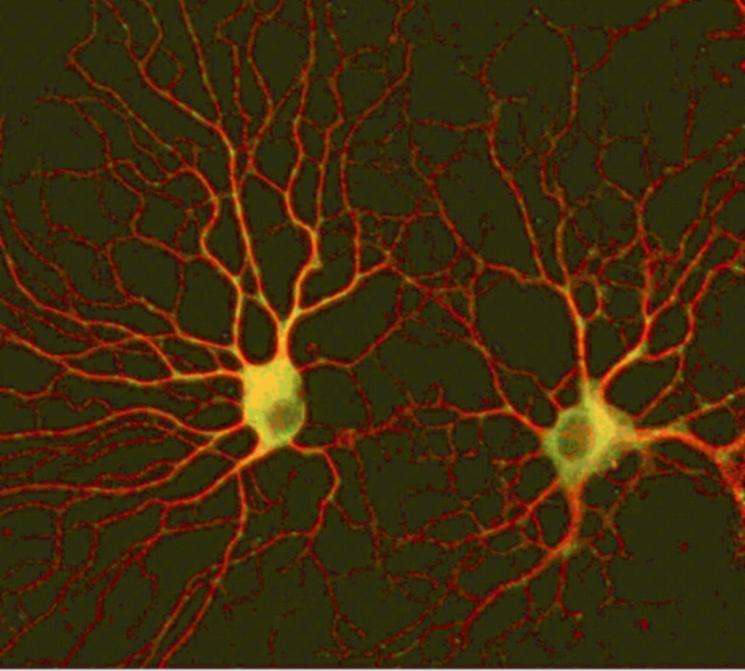

Bild 2: Proteinaggregate im Zellkultur-Modellsystem

Bild 3: Oligodendrozyten in Kultur

Ein anderer Schwerpunkt der Oldenburger Gruppe, gefördert von der Hertie-Stiftung, richtet sich auf die Aufklärung von Vorgängen bei sog. demyelinisierenden Prozessen, die vor allem bei MS eine zentrale Rolle spielen. Myelin ist eine weiße Substanz im Gehirn, die für Nervenzellen von großer funktioneller Bedeutung sind, und für deren Ausbildung eine besondere Gruppe von Zellen, die Oligodendrocyten, zuständig sind. Auch in diesen Zellen werden Proteinablagerungen beobachtet. Die Arbeitsgruppe untersucht an diesen Zellen, die in Kultur gehalten werden können, Signalwege, die die Ausbildung des Myelins fördern und bei krankhaften Prozessen eventuell gestört sind.